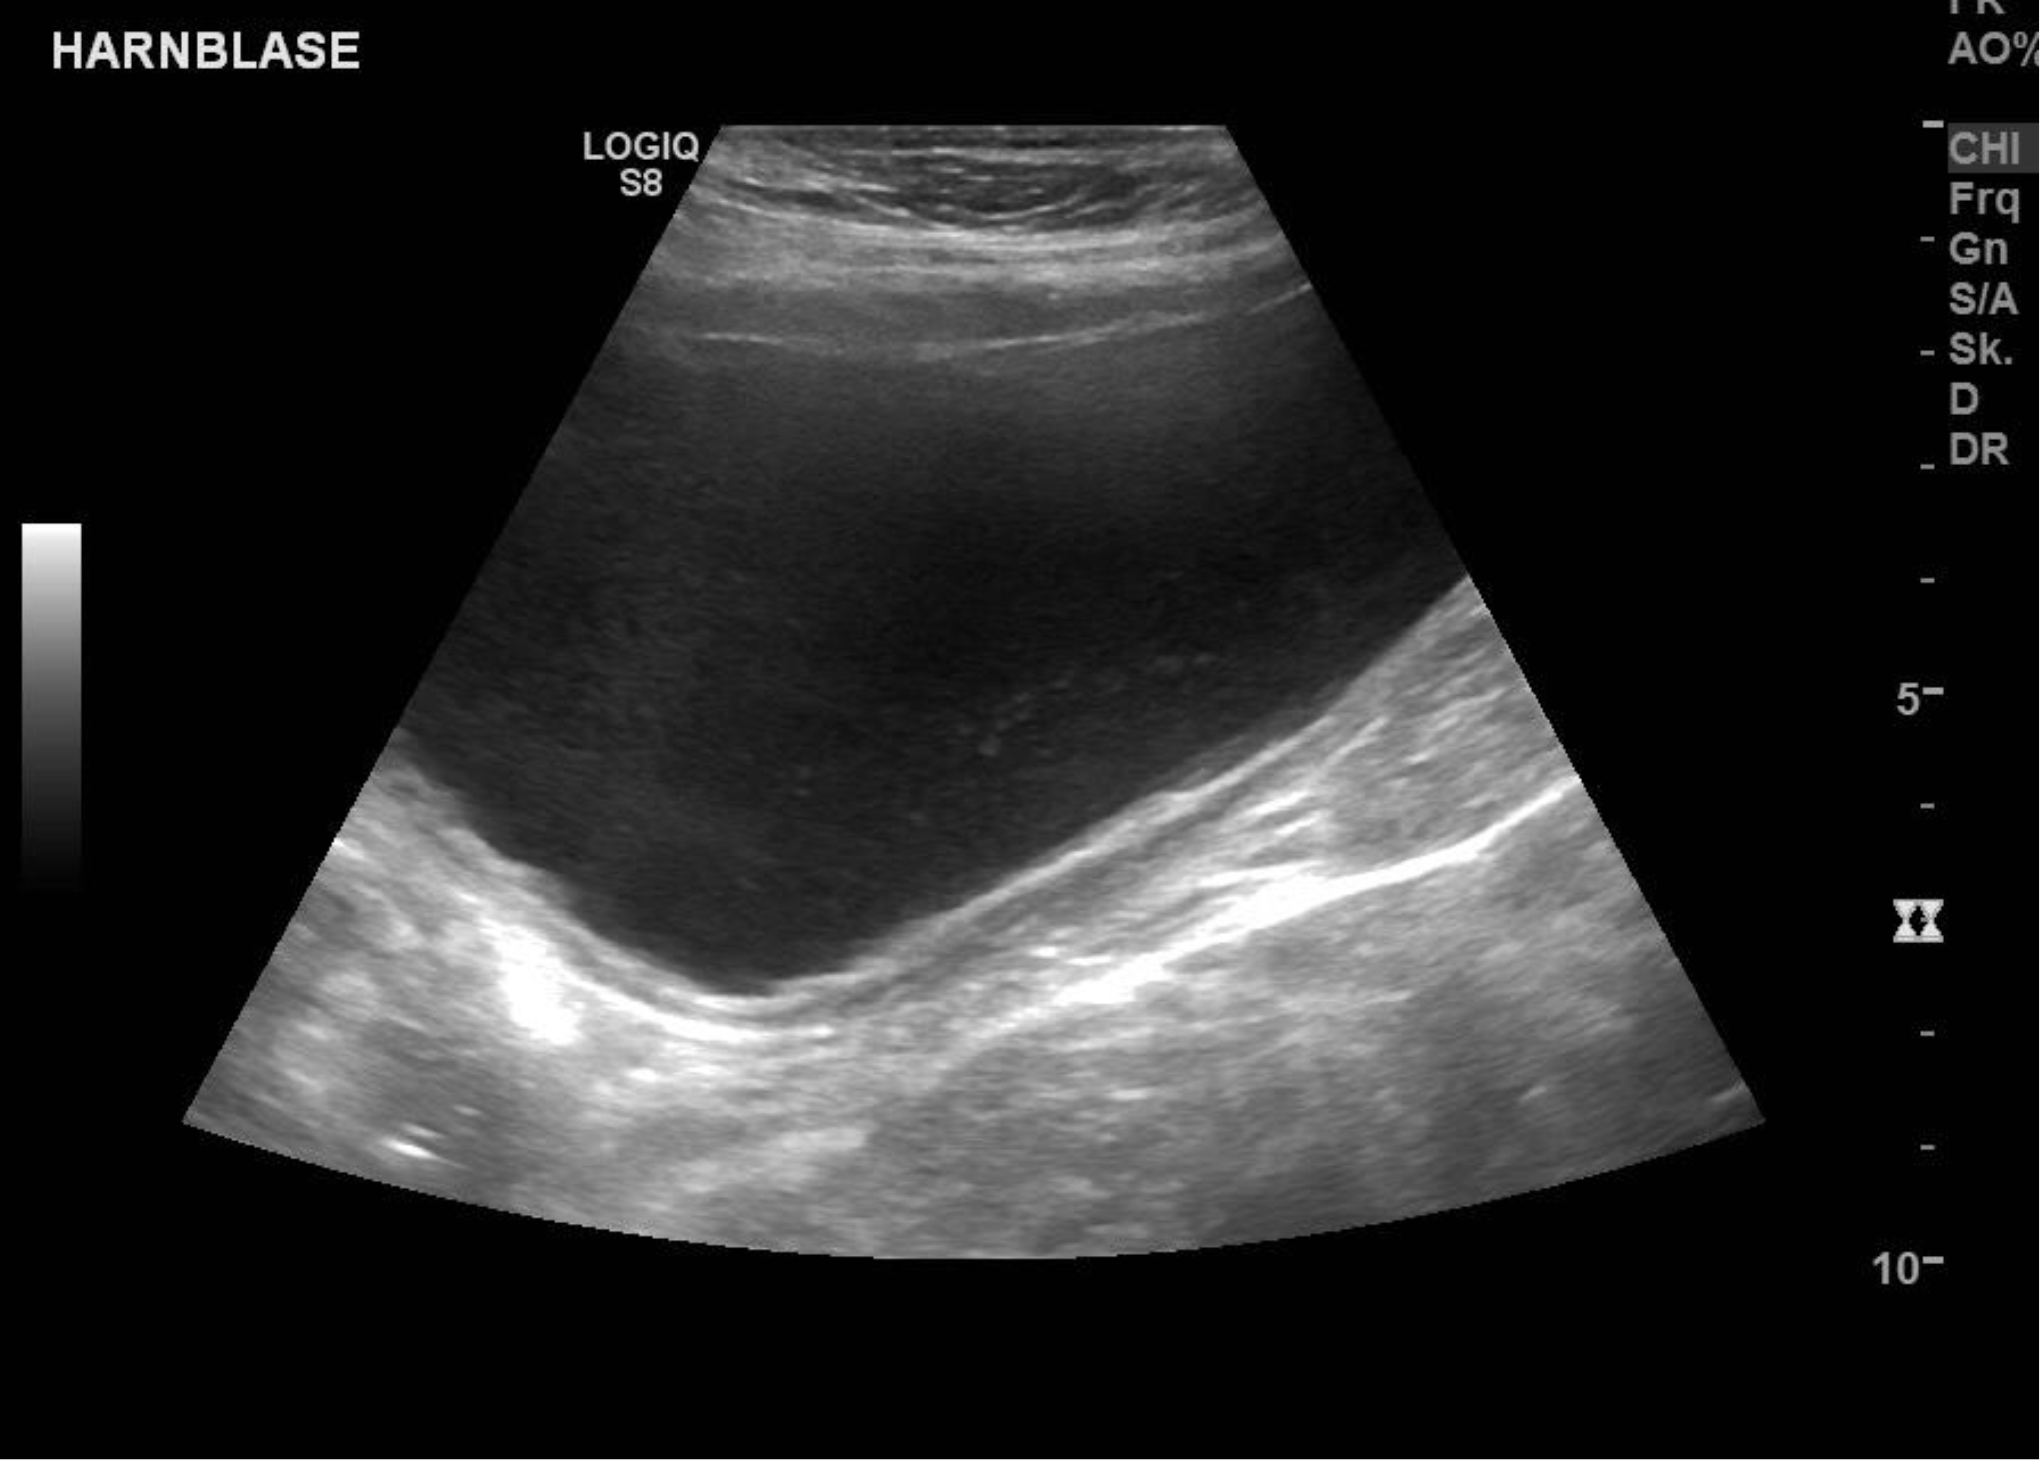

Der Hund kam mit allgemeinen Symptomen wie Unwohlsein/Schwäche, und mit Problemen - verstärktes Trinken und häufiger Harnabsatz, teilweise auch im Haus). In einer unter Ultraschallkontrolle mittels steril entnommener Urinprobe konnten im Sediment bereits mikroskopisch Bakterien nachgewiesen werden. Die Harnblasenwand stellte sich im Ultraschall leicht verdickt (chronisch entzündet) dar.